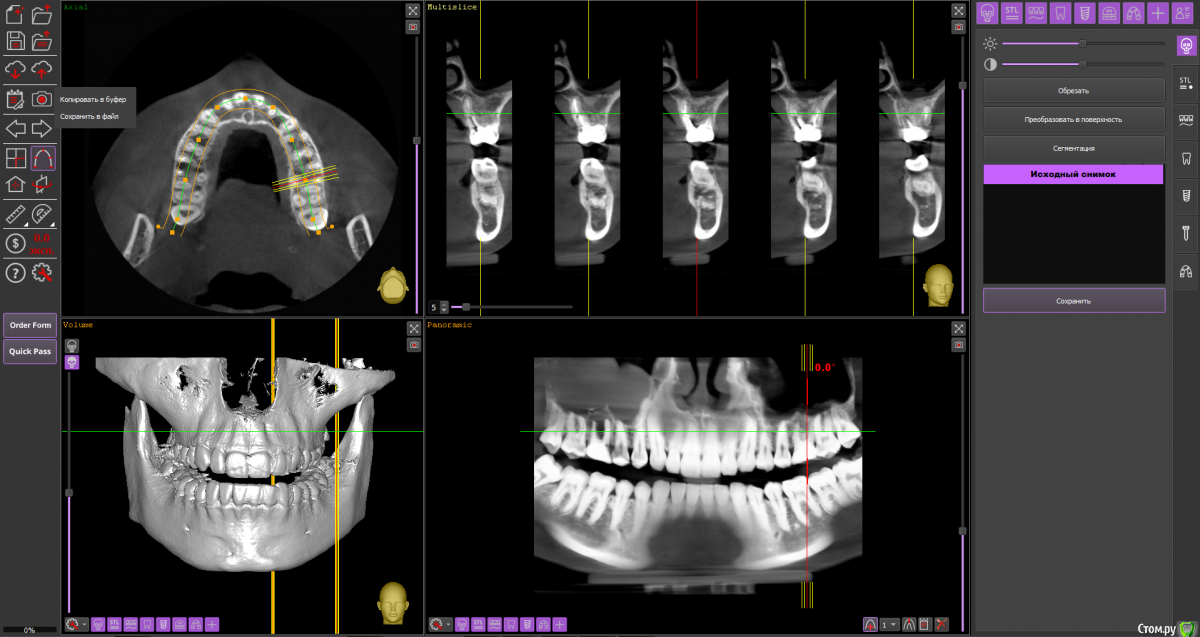

Ольга Вовк Опубликовано 10 февраля, 2021 Поделиться Опубликовано 10 февраля, 2021 Добрый день! Очень прошу помочь по таким вопросам:1. Верхняя шестерка справа - там киста перешедшая в гайморову пазуху (узнала это 4 месяца назад). Зуб ныл 2 года назад, тогда врач просто прописала Аугментин. Все прошло, но опять начал поднывать неделю назад (сейчас опять прошло). Была на консультации, сказали вырывать и прочищать пазуху нужно сейчас, и по приезду уже дальше разбираться. Как лучше быть, если я через неделю уезжаю на 4.5 месяца в страну, где никак не смогу продолжить лечение, а значит ставлю на паузу все на этот период.1. Удалить зуб сейчас, чтоб он зажил и через 4.5 месяца приехав сделать синус лифтинг и ставить имплант, или же ждать это время не удаляя зуб? 2. Не разрушится ли если сейчас не вырвать полностью костная ткань? 3. Можно ли не ставить имлпант, а сдвинуть 7 и 8 зуб к 5ому? Также вопрос по верхней шестерке слева - можно ли ее перелечить под микроскопом, или нужно делать резекцию? Разные врачи сделали разные выводы по нему Ссылка на архив файлов панорамного КТ - http://fayloobmennik.cloud/7414975 Спасибо вам, очень надеюсь на совет Ссылка на комментарий

wladdX Опубликовано 10 февраля, 2021 Поделиться Опубликовано 10 февраля, 2021 (изменено) Зуб 16, мне кажется, лучше удалить до отъезда. Насчёт ортодонтического перемещения 8-го и 7-го на место 6-го, необходимо с ортодонтом очно пообщаться, но на мой взгляд, хирургическое лечение будет более предсказуемым.Зуб 26 может оказаться непростым для эндодонтиста, но если доктор берётся и Вы ему доверяете, то начать стоит с повторного эндодонтического лечения с увеличением. Изменено 10 февраля, 2021 пользователем wladdX 2 Ссылка на комментарий

Ольга Вовк Опубликовано 10 февраля, 2021 Автор Поделиться Опубликовано 10 февраля, 2021 16_1.png 16_2.png 16_3.png 26_1.png 26_2.png 26_3.png 26_4.png Зуб 16, мне кажется, лучше удалить до отъезда. Насчёт ортодонтического перемещения 8-го и 7-го на место 6-го, необходимо с ортодонтом очно пообщаться, но на мой взгляд, хирургическое лечение будет более предсказуемым.Зуб 26 может оказаться непростым для эндодонтиста, но если доктор берётся и Вы ему доверяете, то начать стоит с повторного эндодонтического лечения с увеличением.Спасибо вам огромное! Я так понимаю, что если не удалить сейчас, то тогда к приезду (3 июля) уже совсем костной ткани не останется? Просто если сейчас удалить и будут осложнения, или соустье в гайморову, то я уеду и там не знаю что буду делать в такой ситуации(( Ссылка на комментарий